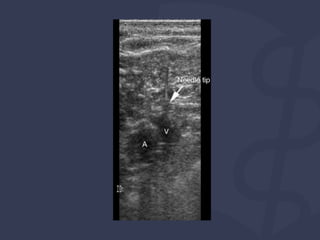

Depois de colocar a agulha, você verá:

⚫ anular artefato devido à agulha

⚫ vaso deformar conforme a pressão aplicada

⚫ Observe a agulha entrando na veia e observe se há

perfuração da parede posterior

Técnica

Longitudinal

Transverse